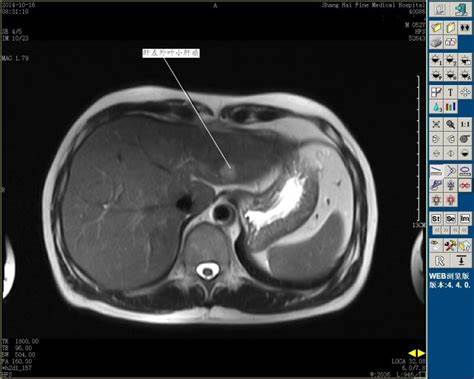

慢性肝病复查,常常要做腹部彩超、CT、核磁共振,如果患者少量吃东西,一般来说影响不是很大。但如果患者吃的过饱,可能有很大的影响。

1.吃得过饱,胃肠道的体积会增大,可能不同程度的遮挡周围的脏器,特别是会导致不容易看清楚肝脏的边缘,甚至掩盖某些细节。

2.胃肠的内容物,会阻挡彩超超声波的穿透,使其后方的器官显示差,或者部分不显示。

3.彩超观察胆囊和胆道系统也是重要的,检查前吃东西,特别是油腻的东西后,胆囊会发生收缩,导致检查的图像不够清晰。